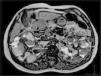

ResultadosSe evaluaron 67 pacientes (59,7% mujeres, edad media 48±14,4 años). Encontramos asociación positiva significativa entre VRT y creatinina sérica o urea, que resultó inversa frente al filtrado glomerular estimado por MDRD-4 y Cockcroft-Gault. Las mujeres mostraron un nivel medio de creatinina sérica y VRT inferior respecto al varón de forma significativa. Los subgrupos afectos de hipertensión arterial e hiperuricemia mostraron valores medios de creatinina sérica, urea y VRT más altos y filtrados glomerulares estimados inferiores. El subgrupo con hipercolesterolemia mostró valores medios de urea más altos y filtrados glomerulares estimados inferiores sin detectarse diferencias significativas respecto al VRT.

ResultsWe evaluated 67 patients (59.7% women, average age of 48±14.4 years) and found a significant positive association between TRV and serum creatinine or urea, which was reversed compared with estimated glomerular filtration by MDRD-4 and Cockcroft-Gault. Women showed an average serum creatinine level and a significantly lower TRV level compared with males. Subgroups affected by arterial hypertension and hyperuricemia presented average values for serum creatinine and urea, higher for TRV and lower for estimated glomerular filtration. The hypercholesterolaemia subgroup showed higher average values for urea and lower for estimated glomerular filtration, without detecting significant differences compared with TRV.